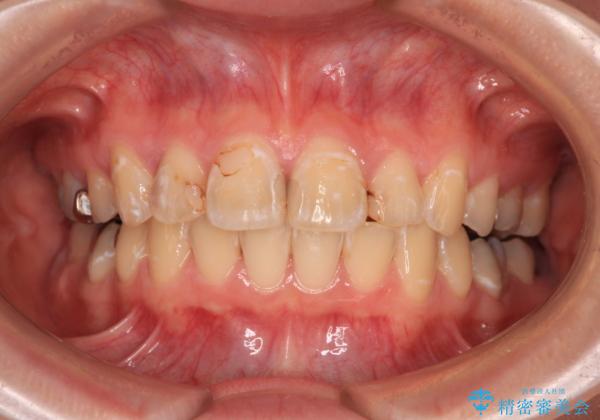

- 上の前歯の出っ歯とでこぼこの歯並びを気にして来院された患者様です。

上下顎歯列ともに前方に突出していましたが、上顎歯列がより前方位にあったため、上顎左右は第1小臼歯を、下顎左右は第二小臼歯を抜歯することとしました。

目立たないワイヤー装置にて抜歯矯正を行うこととしました。